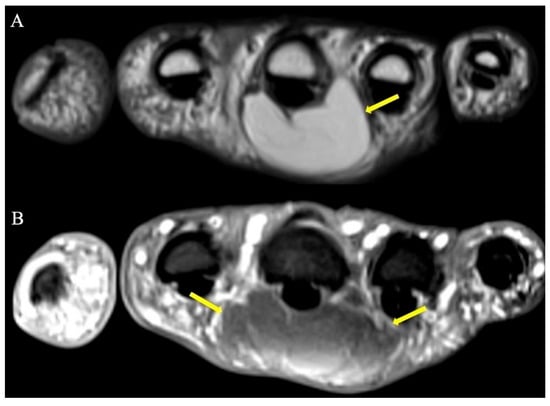

2.8.2. Imaging Appearance

- Murphey, M.D.; Vidal, J.A.; Fanburg-Smith, J.C.; Gajewski, D.A. Imaging of Synovial Chondromatosis with Radiologic-Pathologic Correlation. RadioGraphics 2007, 27, 1465–1488. [Google Scholar] [CrossRef] [PubMed]

- Amary, F.; Perez-Casanova, L.; Ye, H.; Cottone, L.; Strobl, A.-C.; Cool, P.; Miranda, E.; Berisha, F.; Aston, W.; Rocha, M.; et al. Synovial chondromatosis and soft tissue chondroma: Extraosseous cartilaginous tumor defined by FN1 gene rearrangement. Mod. Pathol. 2019, 32, 1762–1771. [Google Scholar] [CrossRef] [PubMed]